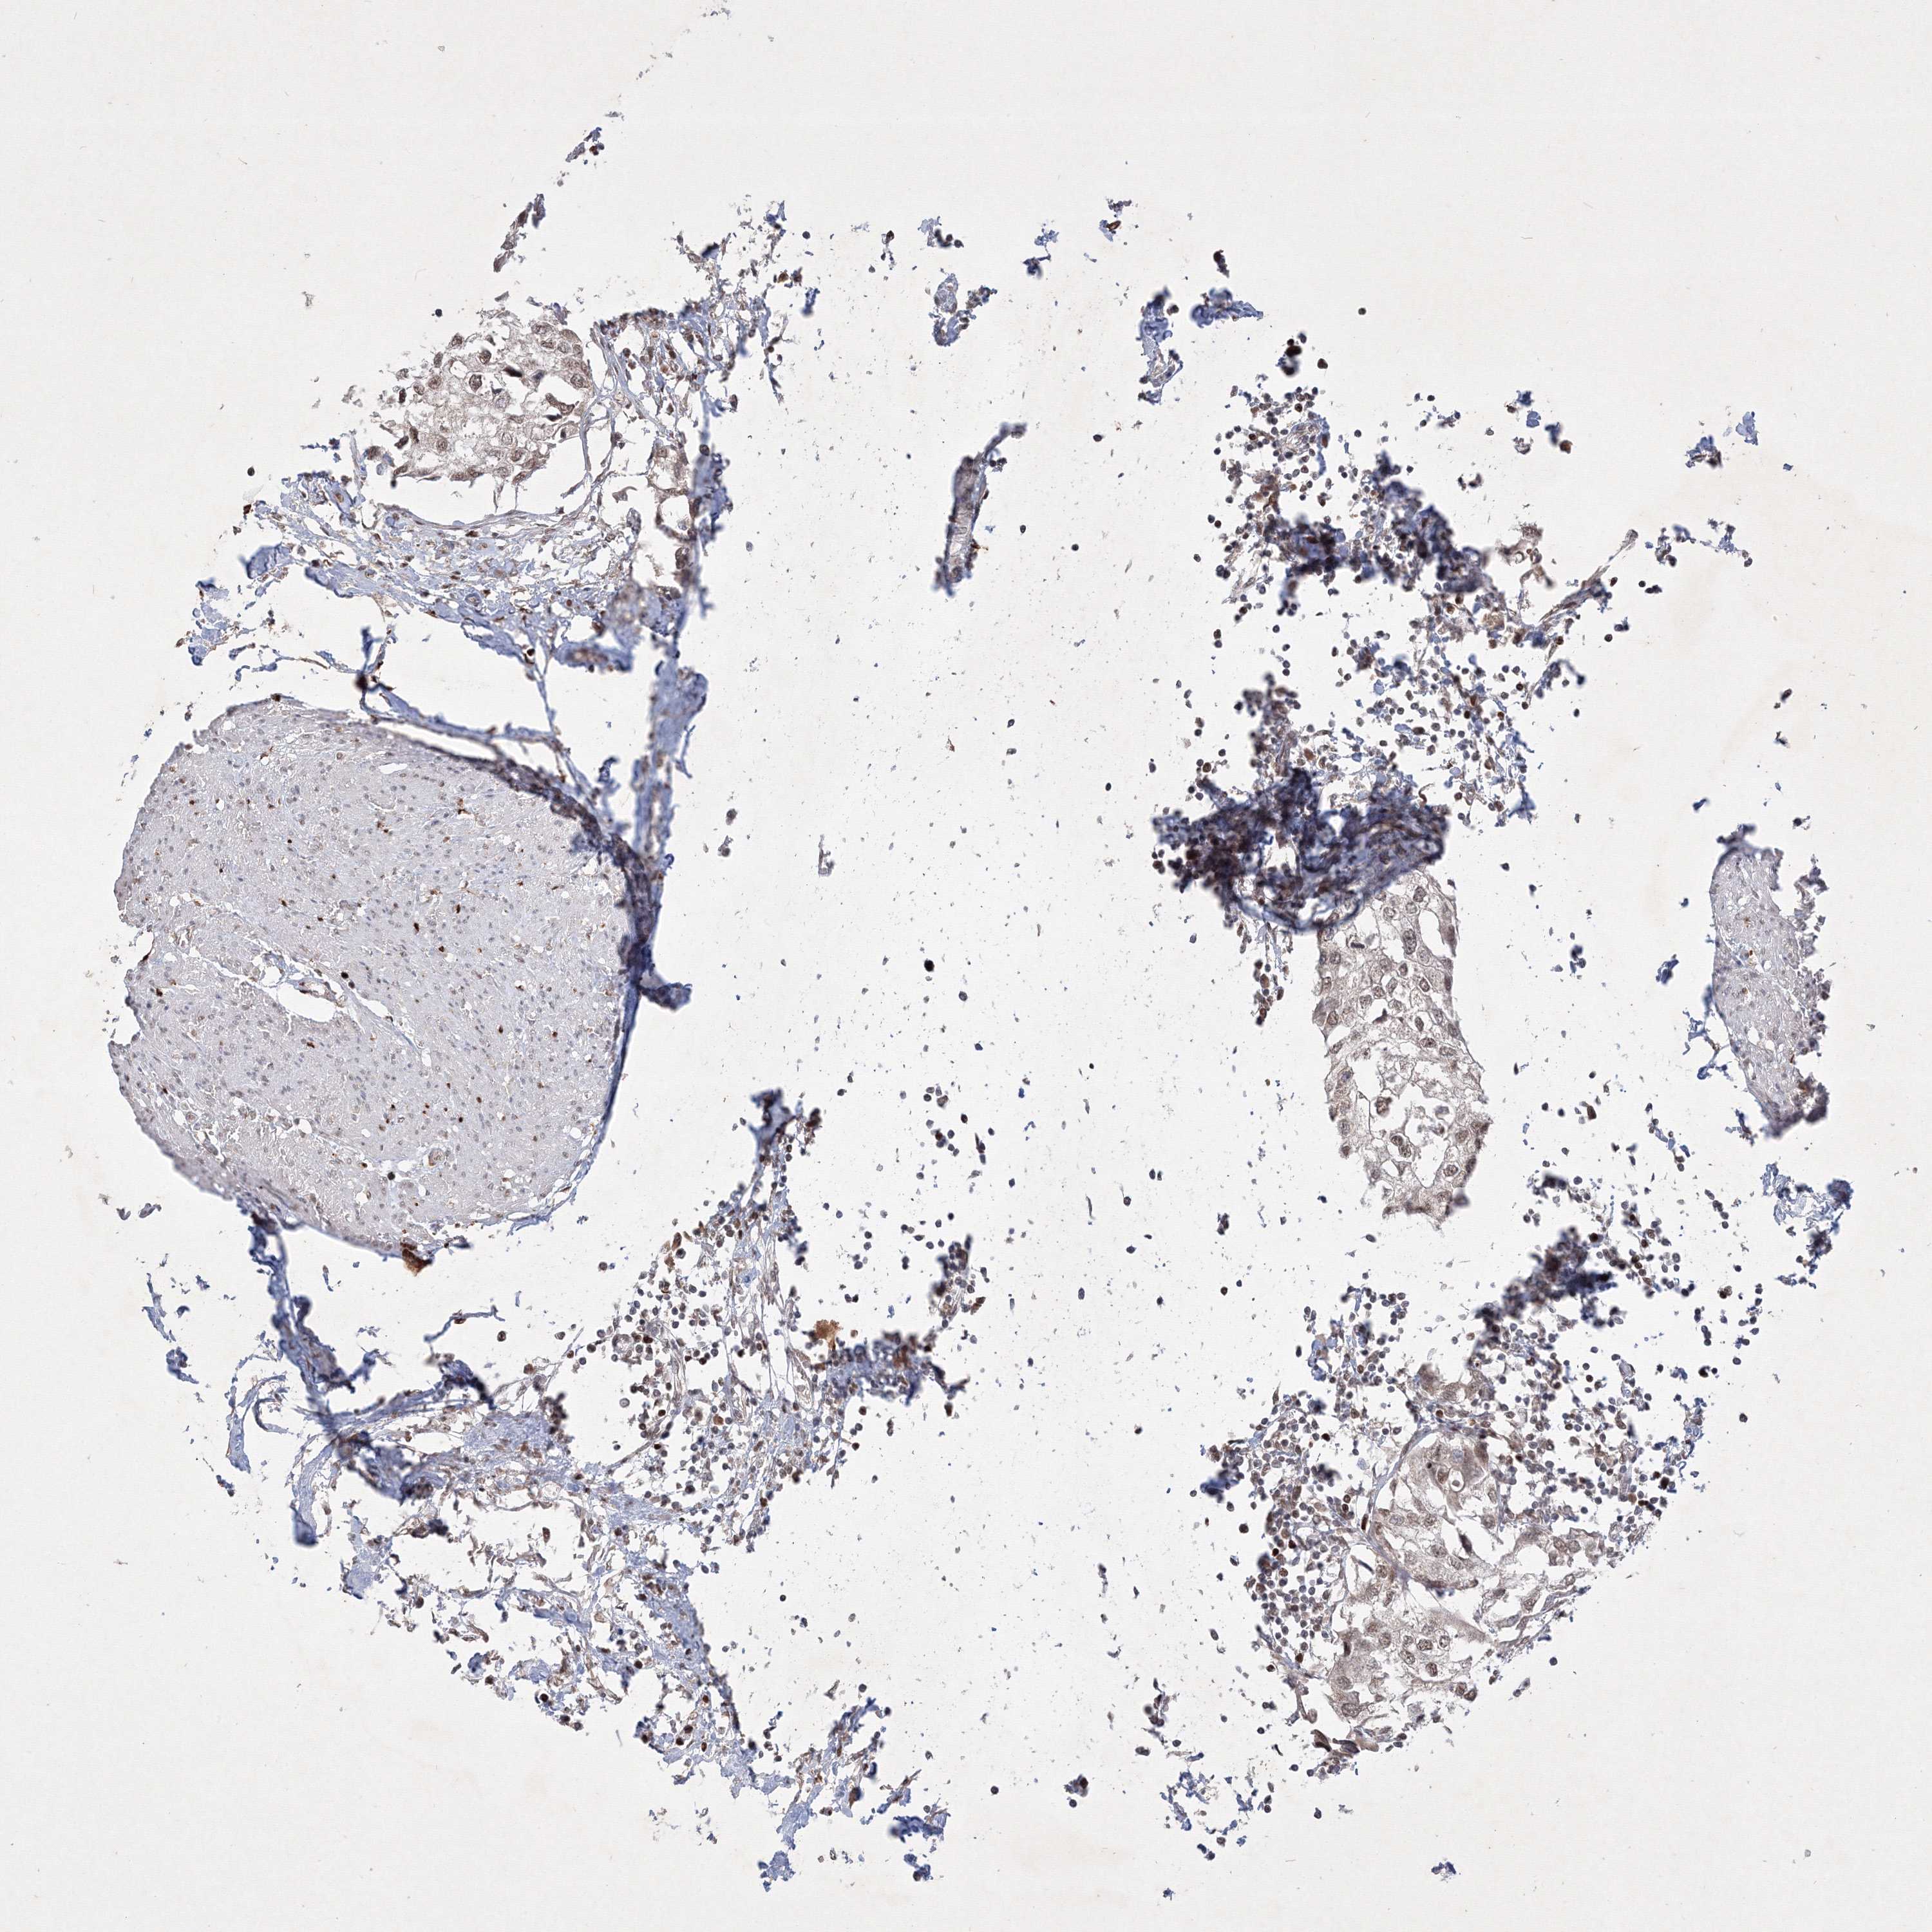

UROTHELIAL CANCER - Protein expressioni

A mouse-over function shows sample information and annotation data. Click on an image to view it in a full screen mode. Samples can be filtered based on level of antibody staining by selecting one or several of the following categories: high, medium, low and not detected. The assay and annotation is described here.

Note that samples used for immunohistochemistry by the Human Protein Atlas do not correspond to samples in the TCGA dataset.

Antibody stainingi

Antibody staining in the annotated cell types in the current human tissue is reported as not detected, low, medium, or high, based on conventional immunohistochemistry profiling in selected tissues. This score is based on the combination of the staining intensity and fraction of stained cells.

Each image is clickable and will lead to virtual microscopy that enables deeper exploration of all samples and also displays staining intensity scores, fraction scores and subcellular localization as well as patient and tissue information for each sample.

Antibody HPA039988

Antibody HPA057104

Antibody CAB032328

Staining

High

Medium

Low

Not detected

Intensity

Strong

Moderate

Weak

Negative

Quantity

>75%

75%-25%

<25%

None

Location

Nuclear

Cytoplasmic/membranous

Cytoplasmic/membranous,nuclear

Urothelial carcinoma, Low grade

Urothelial carcinoma, High grade